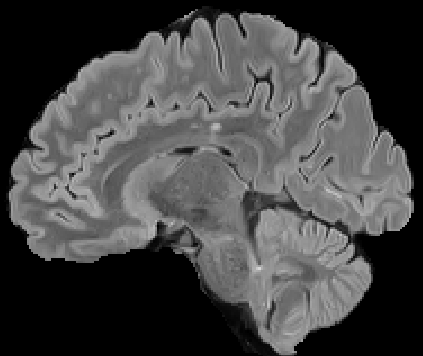

Recently, segmentation methods based on Convolutional Neural Networks (CNNs) showed promising performance in automatic Multiple Sclerosis (MS) lesions segmentation. These techniques have even outperformed human experts in controlled evaluation conditions such as Longitudinal MS Lesion Segmentation Challenge (ISBI Challenge). However state-of-the-art approaches trained to perform well on highly-controlled datasets fail to generalize on clinical data from unseen datasets. Instead of proposing another improvement of the segmentation accuracy, we propose a novel method robust to domain shift and performing well on unseen datasets, called DeepLesionBrain (DLB). This generalization property results from three main contributions. First, DLB is based on a large group of compact 3D CNNs. This spatially distributed strategy ensures a robust prediction despite the risk of generalization failure of some individual networks. Second, DLB includes a new image quality data augmentation to reduce dependency to training data specificity (e.g., acquisition protocol). Finally, to learn a more generalizable representation of MS lesions, we propose a hierarchical specialization learning (HSL). HSL is performed by pre-training a generic network over the whole brain, before using its weights as initialization to locally specialized networks. By this end, DLB learns both generic features extracted at global image level and specific features extracted at local image level. DLB generalization was validated in cross-dataset experiments on MSSEG'16, ISBI challenge, and in-house datasets. During experiments, DLB showed higher segmentation accuracy, better segmentation consistency and greater generalization performance compared to state-of-the-art methods. Therefore, DLB offers a robust framework well-suited for clinical practice.